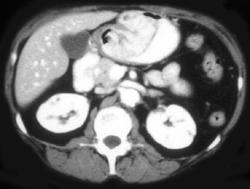

Antral Cancer and Carcinomatosis